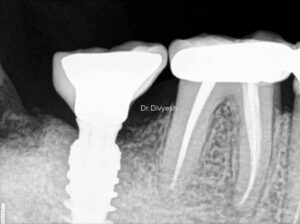

અમારી હોસ્પિટલ માં કરેલ ડેન્ટલ ઇમ્પ્લાન્ટ ના ફોટો